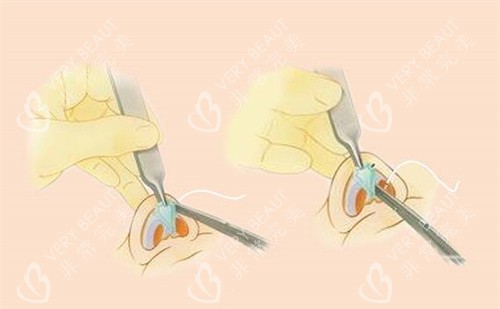

他采用肋软骨微雕重塑鼻部支撑,减少再次变形的风险。创新的取肋技术切口小且位置隐蔽,改善后痕迹不明显。动态平衡技术使鼻部触感柔软,仿生结果良好。

对于多次修复失败的鼻子,如挛缩或穿孔情况,他使用复合材料进行重建。结合自体真皮移植和鼻基稳定术,改善功能并延长形态维持时间。